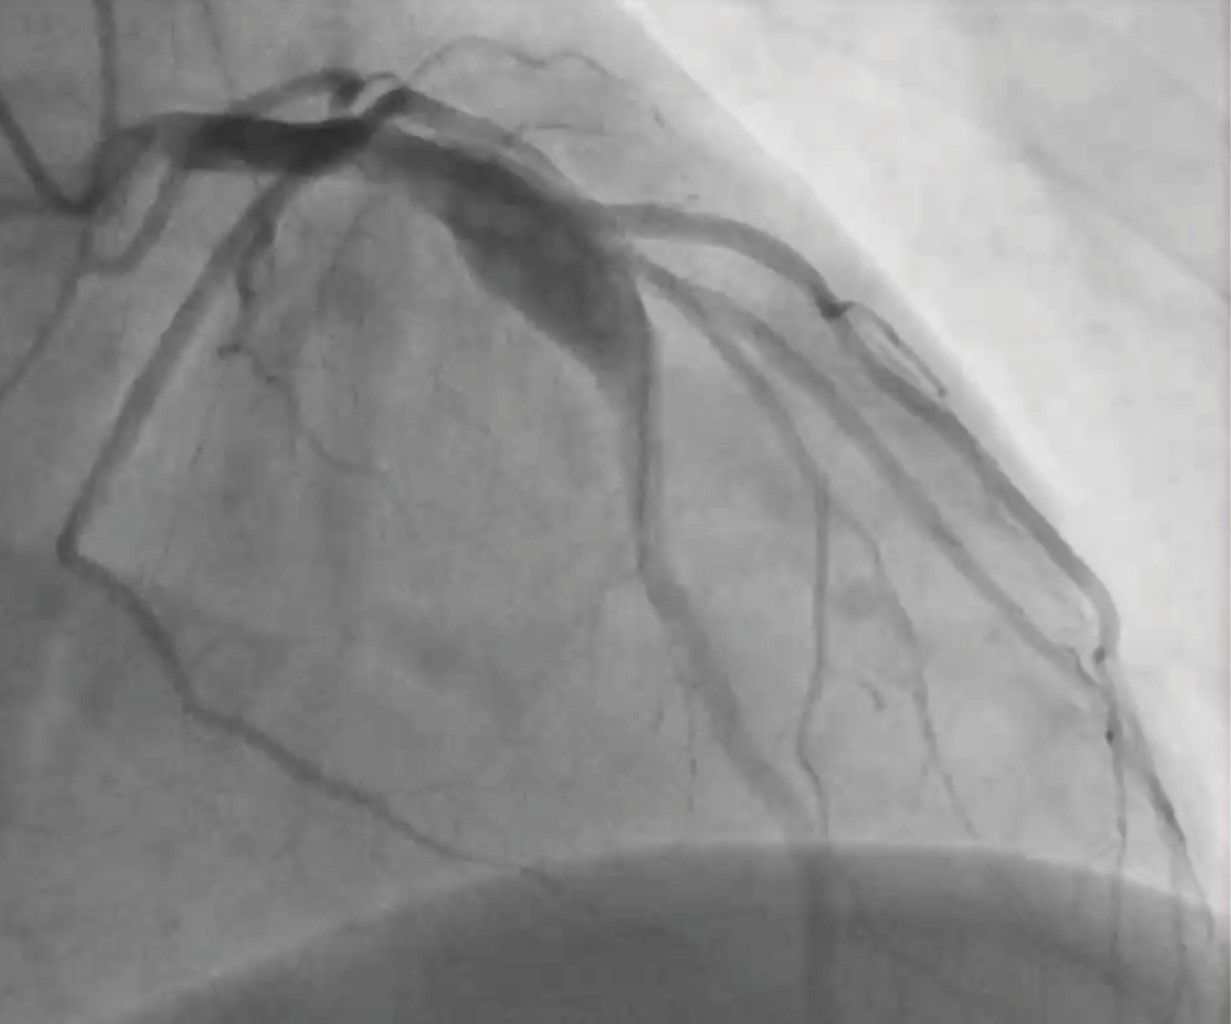

Aneurisma coronario: hallazgo incidental

Guzmán-Salgado JA, Ramírez J, Meza-Carmona J, Hernández-Rendón E, Tarelo-Saucedo JM, Ortega-Romo EE

El aneurisma de la arteria coronaria es una entidad rara en la población general. Presentamos el caso de un paciente masculino de 51 años con angina inestable, en quien se identificó un aneurisma de la arteria coronaria descendente anterior durante la intervención coronaria percutánea. El tratamiento quirúrgico consistió en ligadura, resección y revascularización coronaria, logrando una recuperación satisfactoria y siendo dado de alta cinco días después. La cirugía aneurismática es fundamental en el tratamiento de aneurismas verdaderos, especialmente en pacientes sintomáticos, como medida preventiva y óptima.

Figura 1